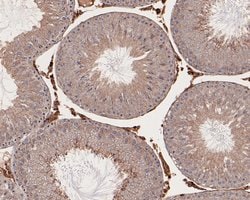

Invitrogen™ RhoGDI Polyclonal Antibody

RhoGDI Polyclonal Antibody for Western Blot, IHC (P)

| Applications | Immunohistochemistry (Paraffin), Western Blot |